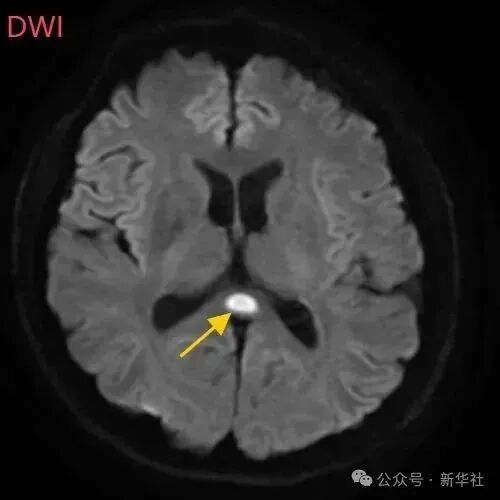

图片

经过一周治疗,小董的胼胝体压部病变明显好转